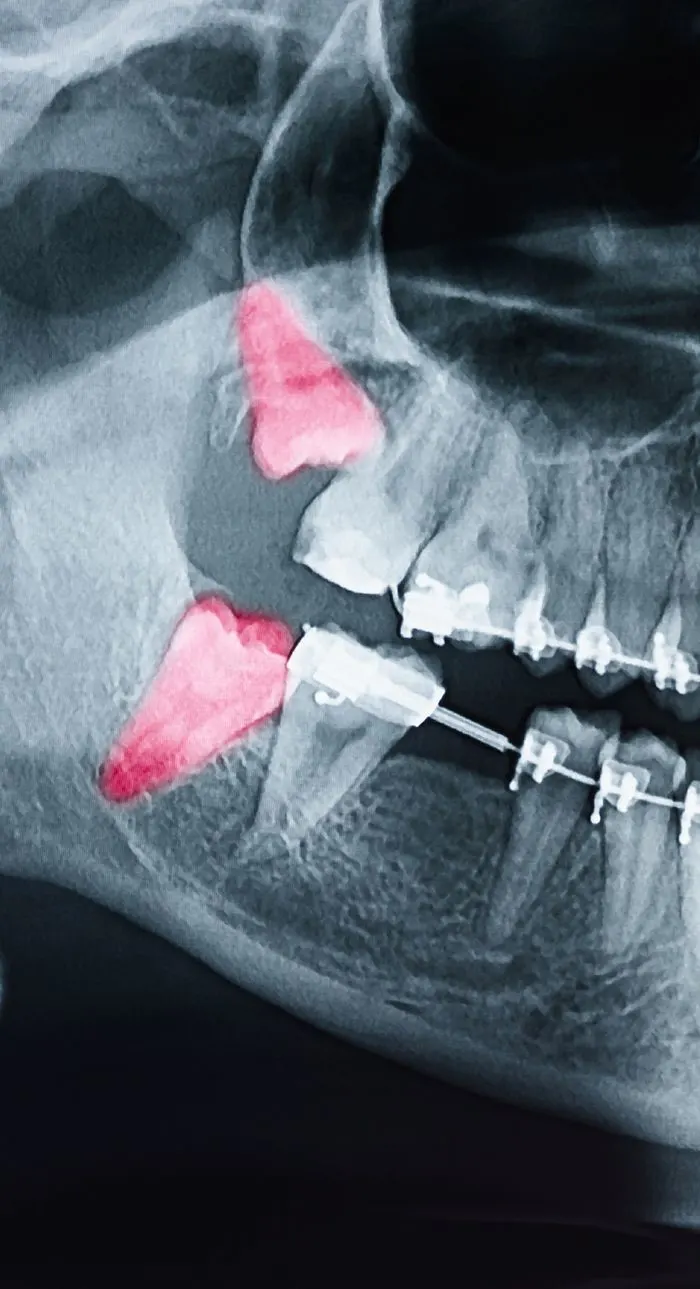

During your consultation, we’ll take digital x-rays to assess the condition of your tooth and the surrounding bone. We’ll explain whether extraction is truly necessary and walk you through any alternatives. If you’re moving forward, we’ll review the number of teeth to be removed, aftercare expectations, and any follow-up recommendations for tooth replacement. We’ll answer every question you have so you feel fully informed and know what to expect.